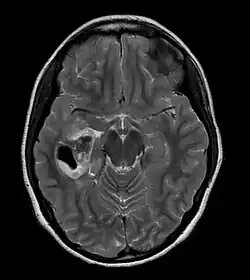

| CT scan of a brain with pleomorphic xanthoastrocytoma. The classic radiographic appearance is one of a superficially situated tumor, here a mural nodule, associated with an underlying cyst. |

Pleomorphic xanthoastrocytoma usually develops within the supratentorial region (the area of the brain located above the tentorium cerebelli). It is generally located superficially (in the uppermost sections) in the cerebral hemispheres and involves the leptomeninges. It rarely arises from the spinal cord.